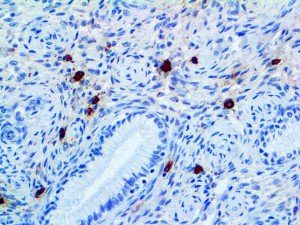

It is the ICU physician who is most likely to witness one of the deadliest manifestations of the abnormal immunological response, the cytokine storm syndrome (CSS). This response is also referred to by some as the cytokine release syndrome (CRS). CSS is characterized by continuous activation and expansion of macrophage and lymphocyte populations, which secrete large amounts of cytokines, causing the cytokine storm. This massive cytokine release is akin to hemophagocytic lymphohistiocytosis (HLH) disease, a syndrome characterized by initial unchecked and persistent activation of cytotoxic T lymphocytes and NK cells.

Clinical and laboratory manifestations of HLH include fever, enlarged liver and/or spleen, neurologic dysfunction, coagulopathy, liver dysfunction, cytopenias (i.e., low levels of erythrocytes, leukocytes, and/or platelets), hypertriglyceridemia, hyperferritinemia, hemophagocytosis, and eventually diminished NK cell activity as the immune system becomes progressively paralyzed. HLH can be familial (primary HLH) or secondary to another disease process (sHLH), such as rheumatic disease, in which it is referred to as macrophage activation syndrome (MAS, characterized by elevated ferritin).